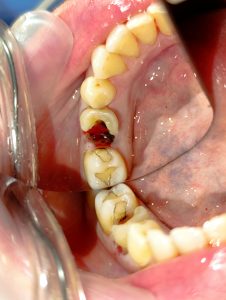

Σπασμένο δόντι

Ο ασθενής έσπασε το δόντι του κατά τη διάρκεια του γεύματος του. Το δόντι ήταν απονευρωμένο και δυστυχώς ο ασθενής καθυστερούσε την κάλυψη και προστασία του δοντιού με θήκη / στεφάνη δοντιού. Αυτό είχε ως αποτέλεσμα το δόντι μετά από κάποιο χρονικό διάστημα να σπάσει και να πρέπει να εξαχθεί από το στόμα το ασθενή. Αν το δόντι είχε προστατευτεί με θήκη, το δόντι θα μπορούσε να είχε σωθεί και ο ασθενής δε θα έχανε το δόντι του.

Τα απονευρωμένα δόντια είναι επιρρεπή στα κατάγματα και γι΄ αυτό το λόγο, είναι σημαντικό να προστατεύονται με θήκη δοντιού, ώστε να μπορούν να διατηρούνται άφοβα μέσα στο στόμα. Αυτό οφείλεται